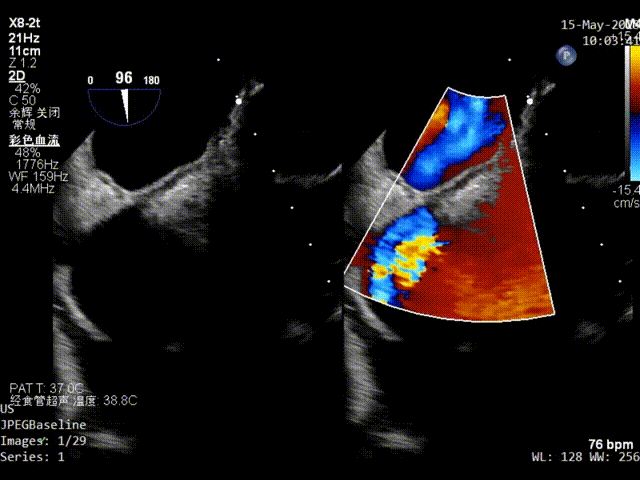

器械进入前TEE彩超影像

一根0.035导丝穿过卵圆孔进入左上肺静脉,形成左心房通路。一根0.035导丝进入上腔静脉,形成右心房通路。

建立通路超声影像